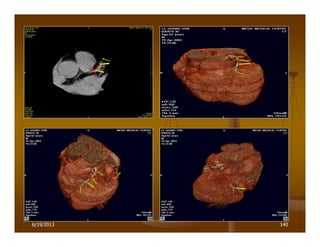

MSCT-AORTIC DISSECTION

PHÌNH ÑOÄNG MAÏCH CHUÛ

(3D-surface display)